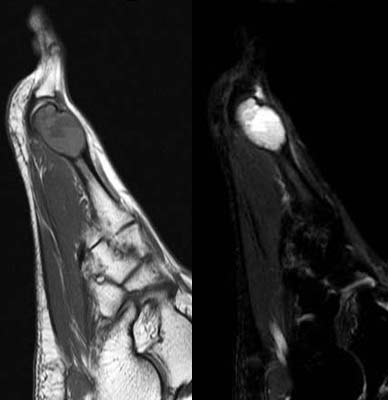

Aneurysmal bone cyst metatarsal. Benign looking expansion of the distal end of the second metatarsal. The lesion is cystic with fluid-fluid levels evident on the STIR image.

16-year-old girl complaing of pain and swelling of the foot.